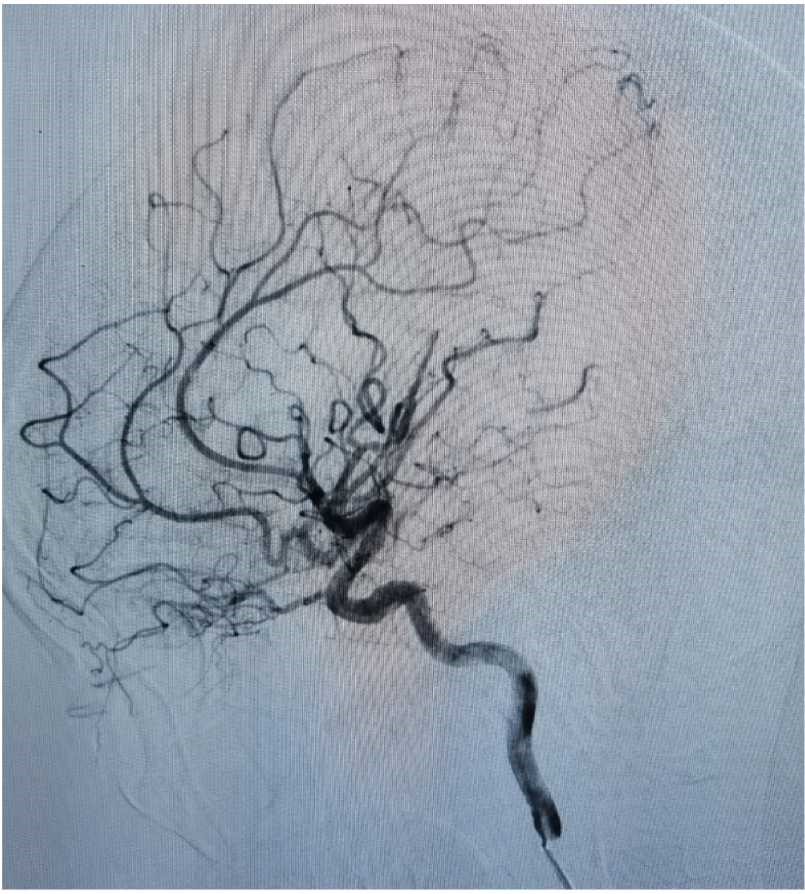

术后复查头CT:无明显出血,且颅骨修补良好。

后患者无明显并发症出现,恢复良好。行DSA检查:见畸形血管团消失。